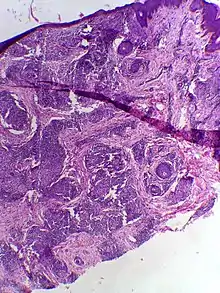

Skin biopsy in tuberculoid leprosy showing multiple peri-appendageal granulomas.

Tuberculoid leprosy is a form of leprosy characterized by solitary skin lesions that are asymmetrically distributed with few lesions and well demarcated edges. There is also early and marked nerve damage. It tends to heal spontaneously.[1]:345 Tuberculoid leprosy is characterized by the formation of epithelioid cell granulomas consisting of a large number of epithelioid cells. In this form of leprosy, Mycobacterium leprae are either absent from the lesion or occur in very small numbers. This type of leprosy is the most benign and the least contagious.[2][3]